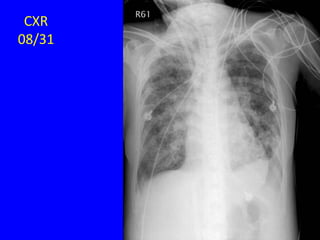

CXR

08/21

08/31